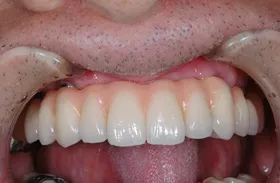

■治療前:奥歯が無いため噛み合わせが深く下の歯が全く見えない

噛み合わせが低いため全体的に歯が削れている

■治療後:下顎 左下5・6番、右下4・6番にインプラント治療

その他の歯に補綴治療をしたことにより、奥歯もしっかりと咬むことができ、奥歯ができたことにより噛み合わせも上がって下の歯も見えるようになり、審美的にも改善された

| 主訴 | 歯科治療をしても歯がすぐに欠けてしまう 奥歯が無いため、奥歯で咬めない |

| 治療方法 | インプラント治療 + 補綴治療 |

| 治療期間 | 約1年 |

| 通院回数等 | 約20回 |

| 費用 | 約250万円(税込) |

| リスク・副作用 | 術後の腫れ・痛み |